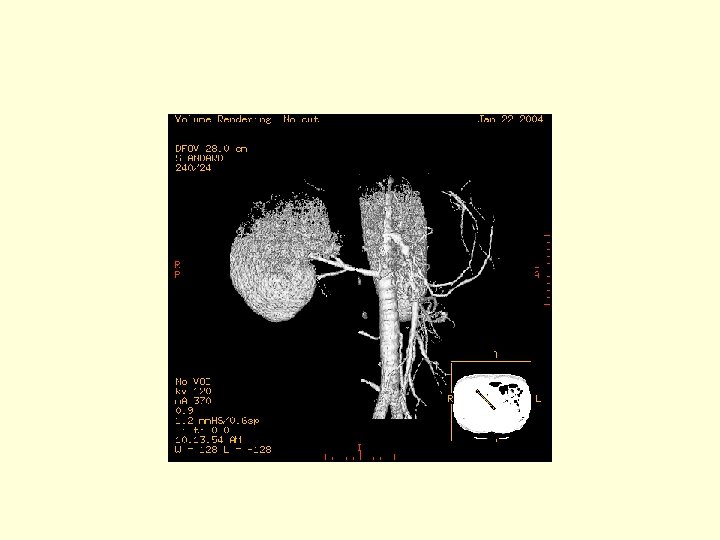

This is a 3 D image showing the branches of the SMA.

This is another 3 D image showing the vasculature of the SMA. Click through the next 20 frames to rotate the image.